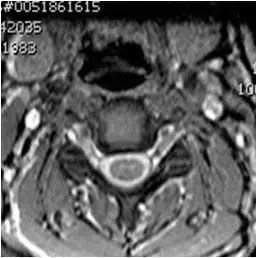

图38、轴向T2梯度回波图像。椎间盘突出与压迫硬膜囊。 轻度左钩椎关节肥大。

图39、轴向T2梯度回波图像。 左侧后外侧椎间盘突出伴压迫囊的前方。

图40、轴向T2梯度回波图像。椎间盘突出伴压迫硬膜囊前部。 注意到脊髓变形。 有椎管狭窄。 没有发现颈髓病。